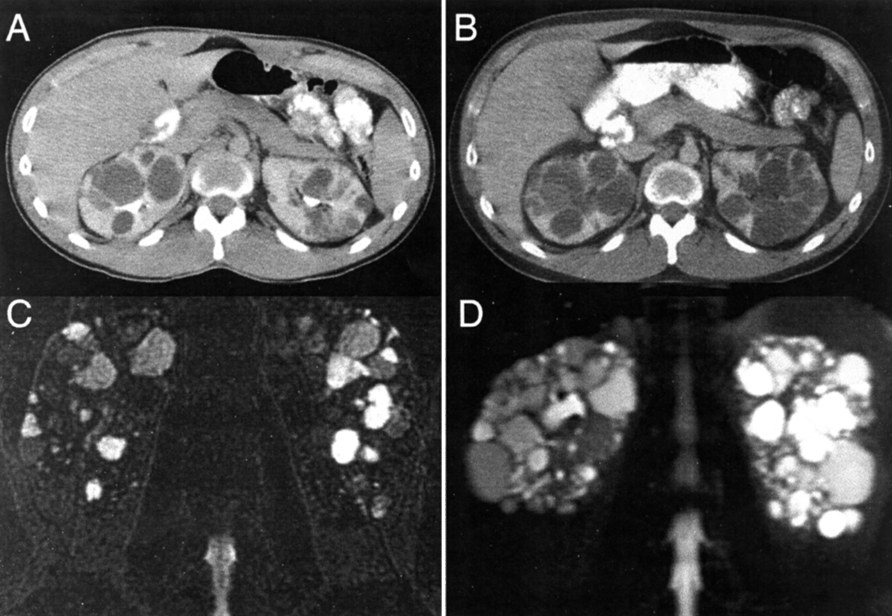

Polycystic kidney disease PKD

U/S or CT scan